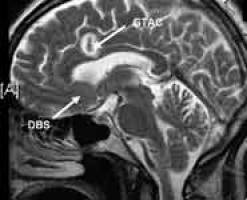

Press release issued 24 January 2011 Pioneering neurosurgical treatment, a world first in Bristol, which very accurately targets brain networks involved in depression, could help people who suffer with severe and intractable depression.